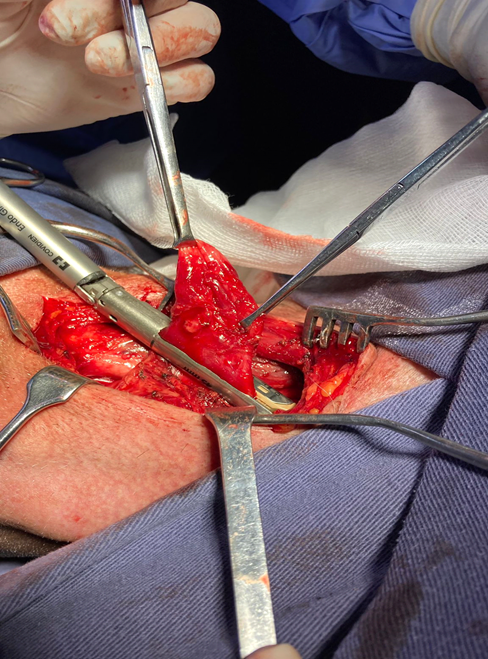

Once the diverticular pouch is identified, it is dissected and released by means of a blunt and gentle maneuver until the neck of the pouch is identified on the posterior pharyngeal esophageal surface. Technically, traction with Allis or dissecting forceps is useful (Figure 6).

Figure 6 Identification and dissection of the diverticular sac. The figure shows the diverticulum tracted from the dissecting forceps. The esophagus is accessed through an alveolar plane medial to the vasculonervous bundle. The cervical spine is used to identify the esophagus which is immediately in front of it. The diverticulum must be dissected with blunt maneuvers up to the esophagus (diverticular neck).

Upon reaching the neck, we can clearly identify the cricopharyngeal muscle in the lower sector, which is loaded with American forceps, taking care not to injure the mucosa and submucosa and sectioning it with ligasure or electric scalpel (Figure 7).

Figure 7 Loading of the cricopharyngeal muscle with American forceps. Once the diverticulum is completely dissected, the cricopharyngeal muscle is loaded, taking care not to injure the mucosa or sub mucosa. It is sectioned with vascular sealants.